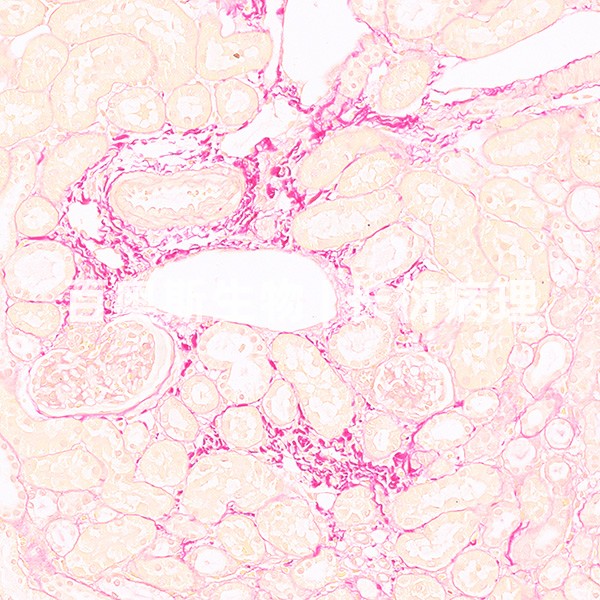

番红固绿染色